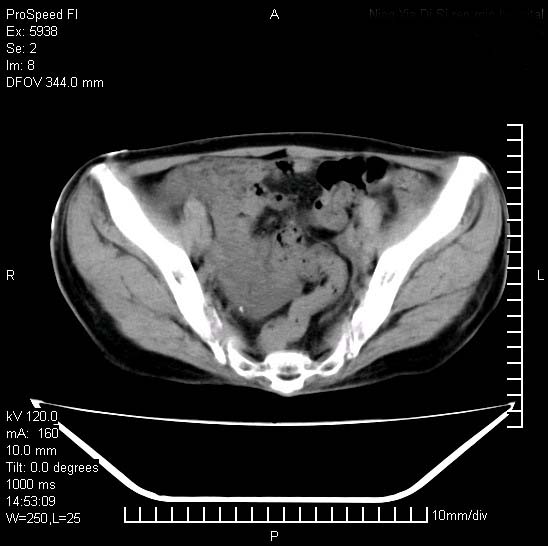

反复小腹疼痛,盆腔积液3年,无发热,曾抗痨一段时间。

右下腹肠管壁增厚,边缘有侵润改变及点状低密度影,内侧可见局限性肿块。考虑-----淋巴瘤或增生型肠结核----盆腔积液-----建议肠镜检查

考虑盆腔及右下腹感染性病变(结核可能)。

结核性腹膜炎伴积液。右侧髂骨骨窗看看,是否有骨质破坏。